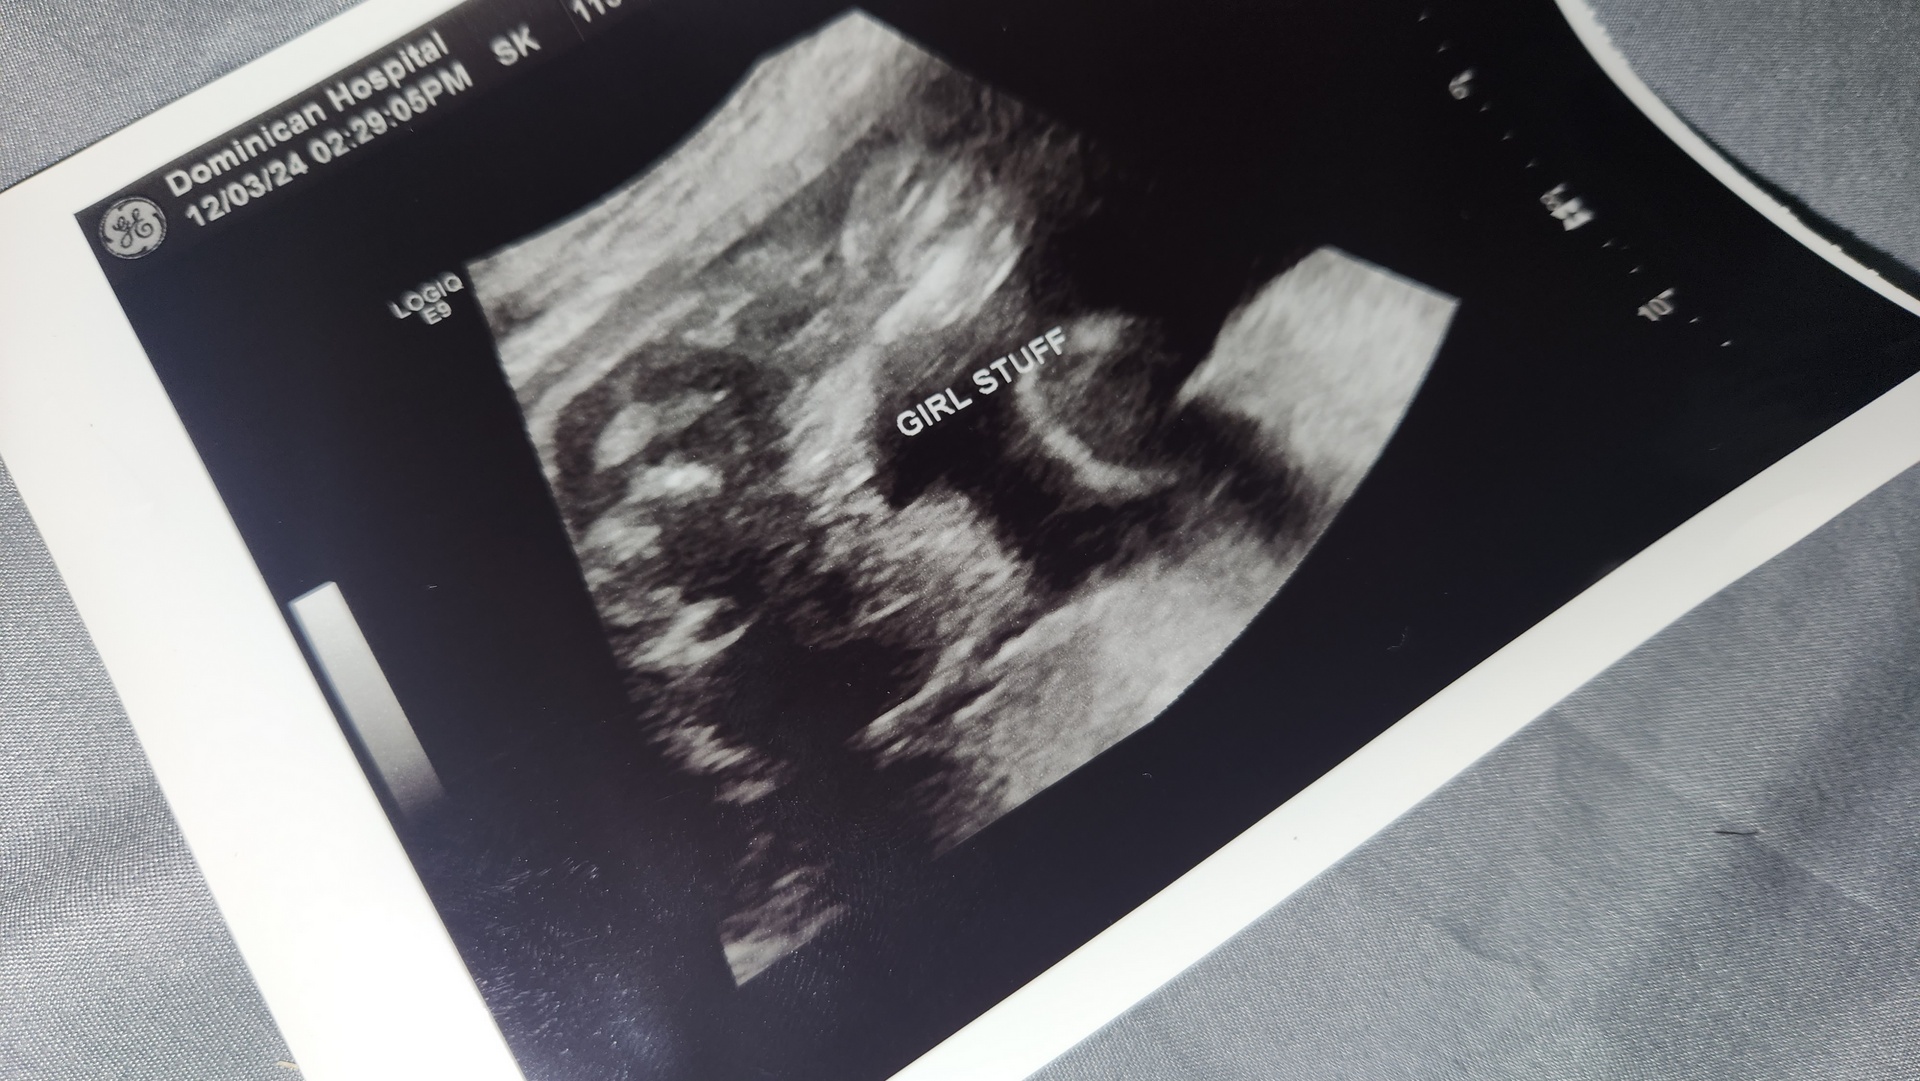

May 12th, 2024 - Mother's Day. What started as a nice Sunday ended up turning into the beginning of the rest of our lives 💙